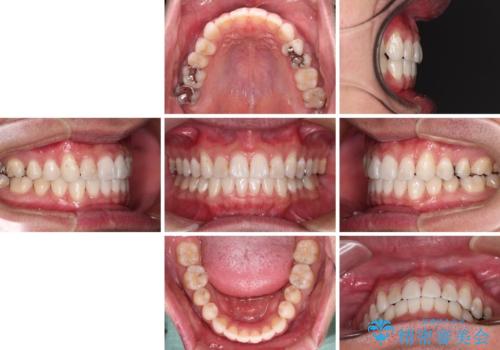

【モニター】 インビザライン・ライトによる軽微叢生の矯正治療

- 30代男性

- インビザライン・ライト

- 4ヶ月

- 2-5回

- 上下前歯の叢生を気にして来院された患者様です。

費用を抑え、期間もあまりかけずに治療をしたいとのことで、インビザライン・ライトを用いて矯正治療を行うこととしました。

- 治療費の目安: 45万円(税込)費用は治療当時の料金となります

インビザライン・ライトは、製作できるアライナーの枚数に制限があるため、移動可能な量に限りがあります。

一方で、半年から1年程度で治療を終えることができるため、軽度の歯列不正の患者様には大変お勧めです。